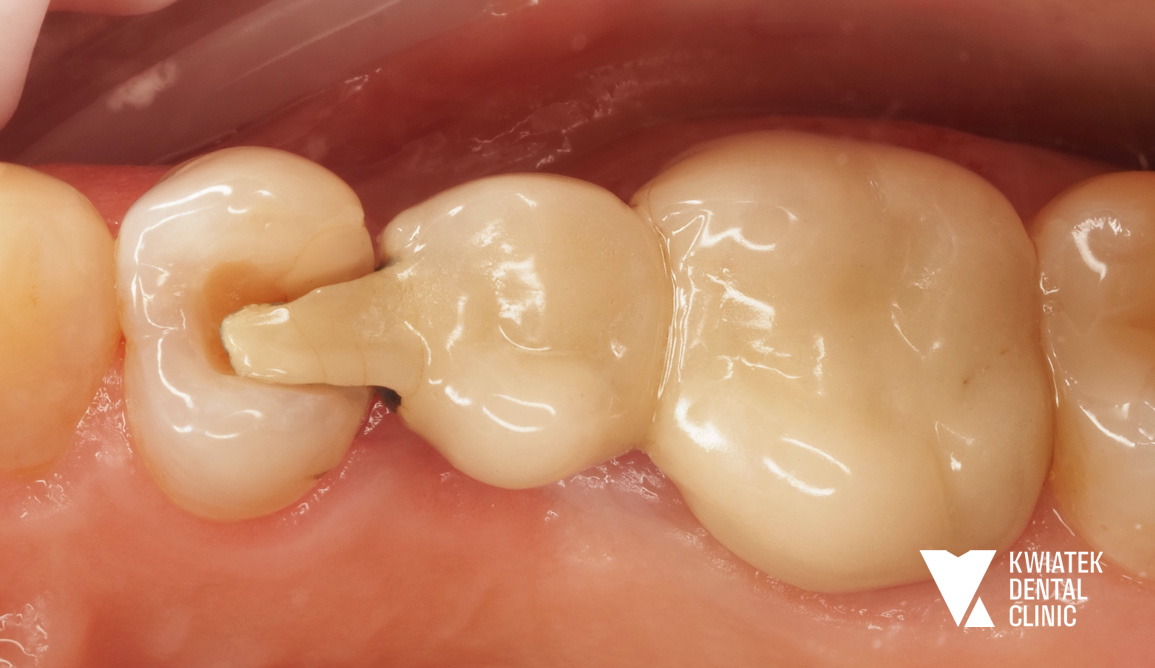

Implant zamiast kompromisu - funkcja i estetyka na najwyższym poziomie

Pacjentka przez lata użytkowała starą pracę protetyczną w odcinku 16 do 14, która z czasem przestała spełniać zarówno funkcję estetyczną, jak i funkcjonalną. Po szczegółowej diagnostyce zaproponowano najnowocześniejsze i najbardziej przewidywalne rozwiązanie w postaci implantacji w miejscu brakującego zęba 15 oraz wykonanie nowych koron ceramicznych. Efektem jest trwała, komfortowa i naturalnie wyglądająca odbudowa, przywracająca prawidłowe warunki żucia i harmonię uśmiechu.